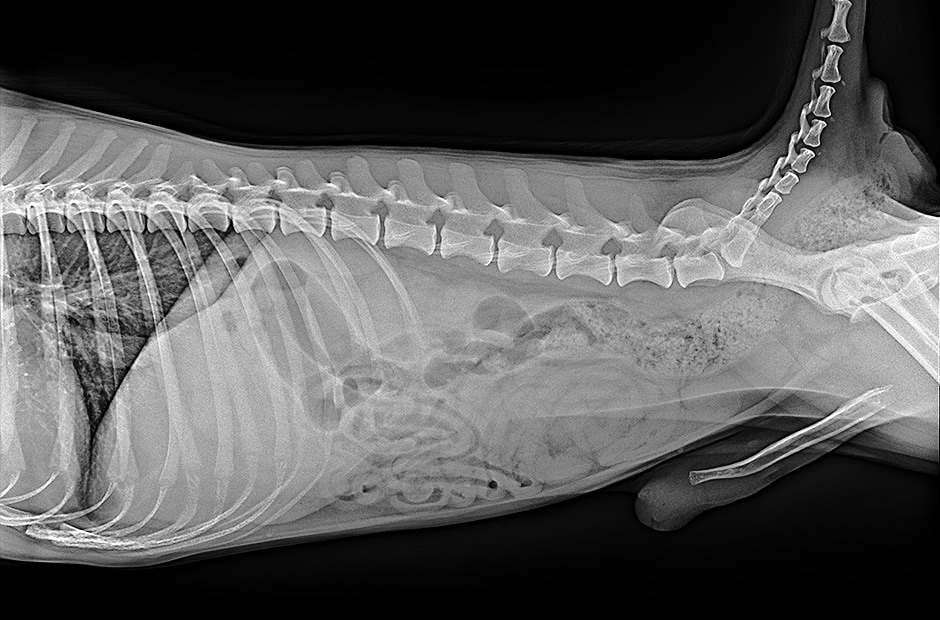

Amélioration de l'efficacité du travail

Disponibilité rapide des images

Disponibilité de l’image brute en 2 secondes avec une connexion filaire, ou 2,5 secondes avec une connexion sans fil

APPLICATION

Application

Radiographie Générale

TYPE TFT

Type TFT

a-Si

SCINTILLATEUR

Scintillateur

Csl

PIXEL PITCH

Pixel Pitch

140 µm

ZONE D’IMAGE

Nombre de Pixels

3072 x 3072 pixels

Zone Active TFT

430.08 x 430.08 mm

MTF

MTF @ 0.5lp/mm (Typ.)

89%

DQE

DQE @ 0.1lp/mm (Typ.)

72%